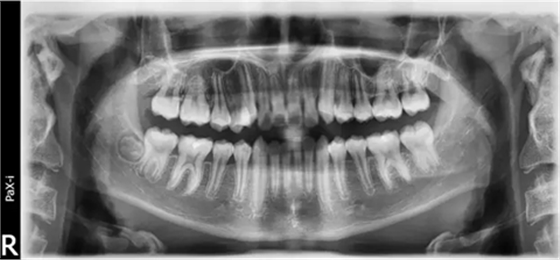

(曲面斷層片)